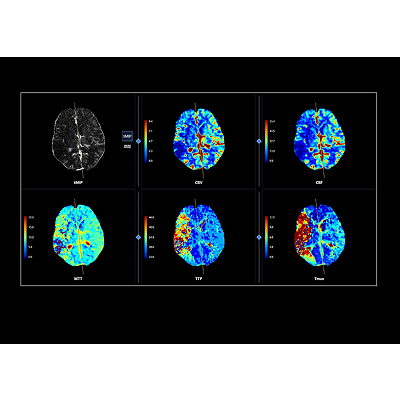

联影智能CTP脑灌注智能分析系统可自动重建灌注参数图(CBV、CBF、MTT、TTP、Tmax)与tMIP图像,精准定位与定量分析低灌注区、核心梗死区及错配(Mismatch)区域,可对CBV、CBF、Tmax进行多阈值分析,支持15个脑区自动分割并提供异常脑区分析,自动生成智能报告,支持智能胶片打印与归档,辅助医生多方位评估患者脑血流灌注情况,精高效诊疗。

联影智能CTP脑灌注分析系统能够定量地分析出核心梗死区、低灌注区与错配区,还能够提供CBF、CBV、Tmax等多参数、多阈值分析,以充足的量化信息为辅助医生全方位精准评估脑血流灌注情况,为患者提供更好的治疗决策。